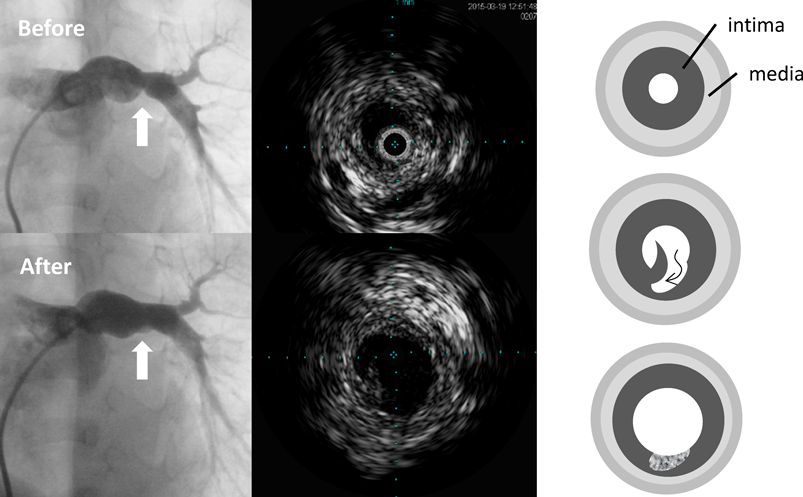

経皮的バルーン血管形成術は,血管狭窄病変を内腔より拡張し,内膜から中膜にかけて一時的な亀裂・解離を生じさせることで,より大きな血管内径へのリモデリングを促し血行再建することを目的とする治療である(Fig. 11).日本先天性心疾患カテーテル治療学会(JCIC)データベースによると,本邦で実施される先天性心疾患カテーテル治療年間約4,500例のうち,経皮的バルーン血管形成術は約1,600例(36%)を占める2).新生児から成人まで幅広い年齢・体格を対象とするとともに,難易度の高いカテーテル治療手技へ向けた基本となるため,先天性心疾患カテーテル治療医を目指す医師にとって習熟すべき手技である.本稿では最も一般的に行われる肺動脈狭窄症に焦点を当て解説する.

Fig. 1 Upper and lower panels show angiographic and intravascular ultrasound findings before and after transcatheter balloon angioplasty, respectively. Intravascular ultrasound shows that a laceration of the intima follows a dissection between the intimal and medial layers, which promote vascular remodeling and achieve a larger diameter of the vessel. Schemes of the vascular remodeling show the pathophysiology of vascular remodeling (the right side).